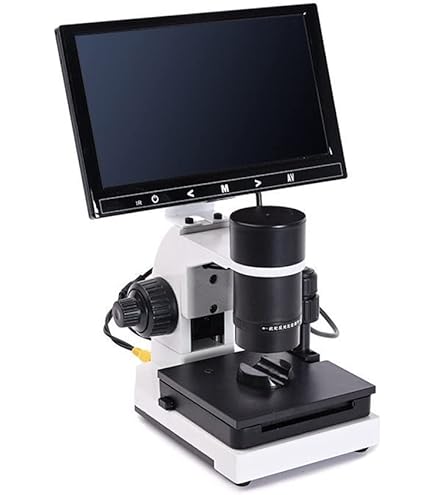

Amazon | 血流スコープ 毛細血管顕微鏡 9インチモニター,

Amazon | 血流スコープ 毛細血管顕微鏡 9インチモニター, 血流観察拡大鏡スコープカメラ/M2587TK-100B | シロ産業 |,

血流観察拡大鏡スコープカメラ/M2587TK-100B | シロ産業 |, 毛細血管スコープ Bscan-ZD 研究セット|顕微鏡・光学機器|製品

毛細血管スコープ Bscan-ZD 研究セット|顕微鏡・光学機器|製品 大画面の9インチモニター付きの「新品未使用品」の血流スコープです。(98,553円の商品をヤフオク専用の特別価格で販売しています。)他の商品は倍率が低いため、血流が見えにくいという欠点がありました。そのため、このモデルに買い換えた方も中にはいらっしゃっいました。この商品は市販品の中では「最も高倍率」の血流スコープになります。スマホのカメラに例えると「望遠レンズ」になりますので、大きく見ることができます。また、血流スコープの見やすさはレンズの大きさに比例します。以前、購入された方から「20万円する商品よりもよく見える!」との感想を頂きましたが、その理由は、鏡筒(レンズ)が大きいからです。安いスマホのカメラは画質が悪く、iPhoneのカメラの画質がいい理由の1つは、レンズが大きいからです。他社の商品よりも、くっきりと大きく写りますので、血流の流れを鮮明に確認する事ができます。1枚目から4枚目の商品の写真は、仕様変更前の写真になります。商品の改良で、下部のレンズが少し大きくなり、更に見やすくなりました。お送りする商品の写真は5枚目~9枚目をご確認ください。付属のモニターでも「ipad mini」より大きな画面で見ることができます。また、テレビのRCA端子に接続して、大画面テレビで見ることも可能です。(コードを購入する必要はありません。)日本語の説明書が付いていますので、接続に不安がある方もご安心下さい。ピントを合わせると、かなり鮮明に写りますので、運動後に確認をすると、血流がかなり早くなっていることもしっかりと確認できます。また、高倍率のため、ゴースト血管のチェックもできます。実際の使い方ですが、薬指の爪の甘皮の部分にオイルを付けて、毛細血管を観察します。オイルはどのオイルでも問題なく見ることができますので、家庭にあるオリーブオイルや食用油をご利用下さい。持ち運びをする時は、付属のアルミニウムケースをご使用下さい。なお、テレビで見るときは白黒になりますが、カラーで見たい方は変換器を購入すると、カラーで見ることができます。円安でかなり仕入れ価格が上がっていますが、価格をかなり抑えて販売していますので、よろしくお願い致します。